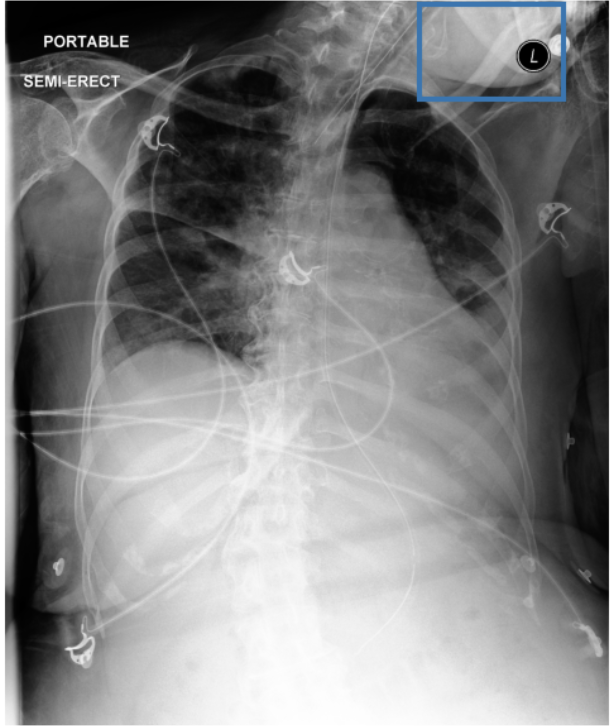

Figure 3 shows phrase grounding results for the phrase “Chronic inflammatory changes predominantly in both lung apices” on an image from PadChest-GR [11]. Both CURE and MAIRA-2 successfully identify the lung apices associated with the described findings. However, CURE’s localization is more accurate and better aligned with the phrase semantics, while MAIRA-2 provides a coarser prediction that only partially covers the relevant areas. As expected, MedGemma-4B-IT does not produce visual grounding outputs, and thus no bounding boxes are shown for this model.